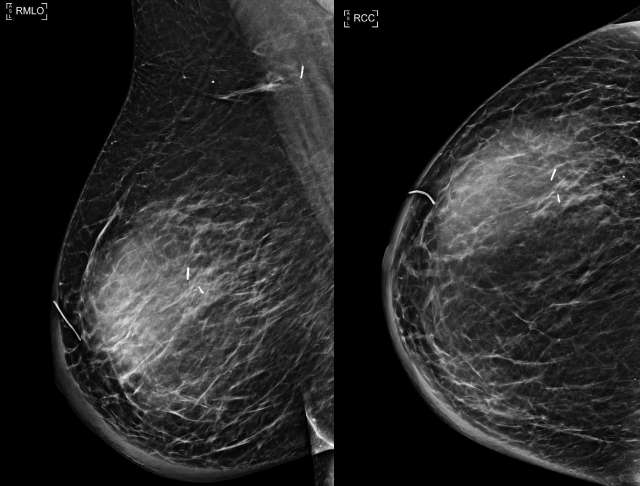

• Mammogram: Water-density masses located at the surgical site, Figure 5.23

Case: Post-Surgical Fluid Collections Figure 5

Figure 5 -Right MLO and CC views demonstrate a mass in the upper outer breast 9 months following lumpectomy and sentinel lymph node biopsy.  Note prominent skin thickening, which corresponds to patient’s lymphedema.